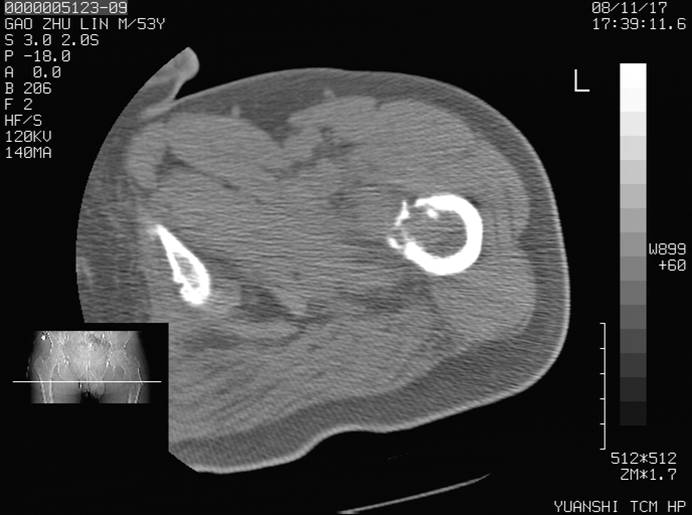

标题: CT16696:M53Y,左股骨上段骨折。 [打印本页]

标题: CT16696:M53Y,左股骨上段骨折。

左股骨上段外伤1个小时,左股骨上段疼痛。村医以腰椎间盘病变给以按摩及理疗数天。

图像不太清楚,左股骨上段外伤性骨折?病理性骨折?

左股骨上段粉碎性骨折

左股骨上段粉碎性骨折;建议上传骨窗看看是不是病理性的啊!

左股骨上段粉碎性骨折,不排除病理性骨折可能。

考虑骨肉瘤伴病理骨折

考虑:骨肉瘤伴病理骨折.

病理性骨折,考虑转移所致.